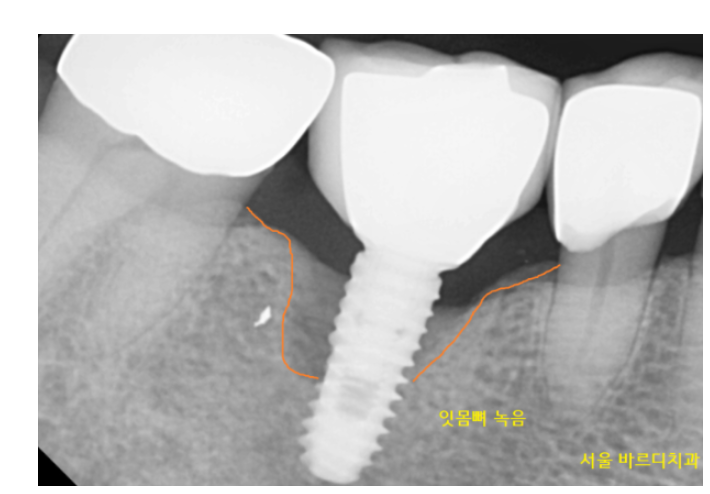

임플란트에 염증이 생겨도

심한 치주염일 경우에도

잇몸 물집, 고름에 활용 등등

잇몸 만능 통치약이랄까요~?

230116 임플란트 주위염에도 적극적으로 활용되고 있습니다.